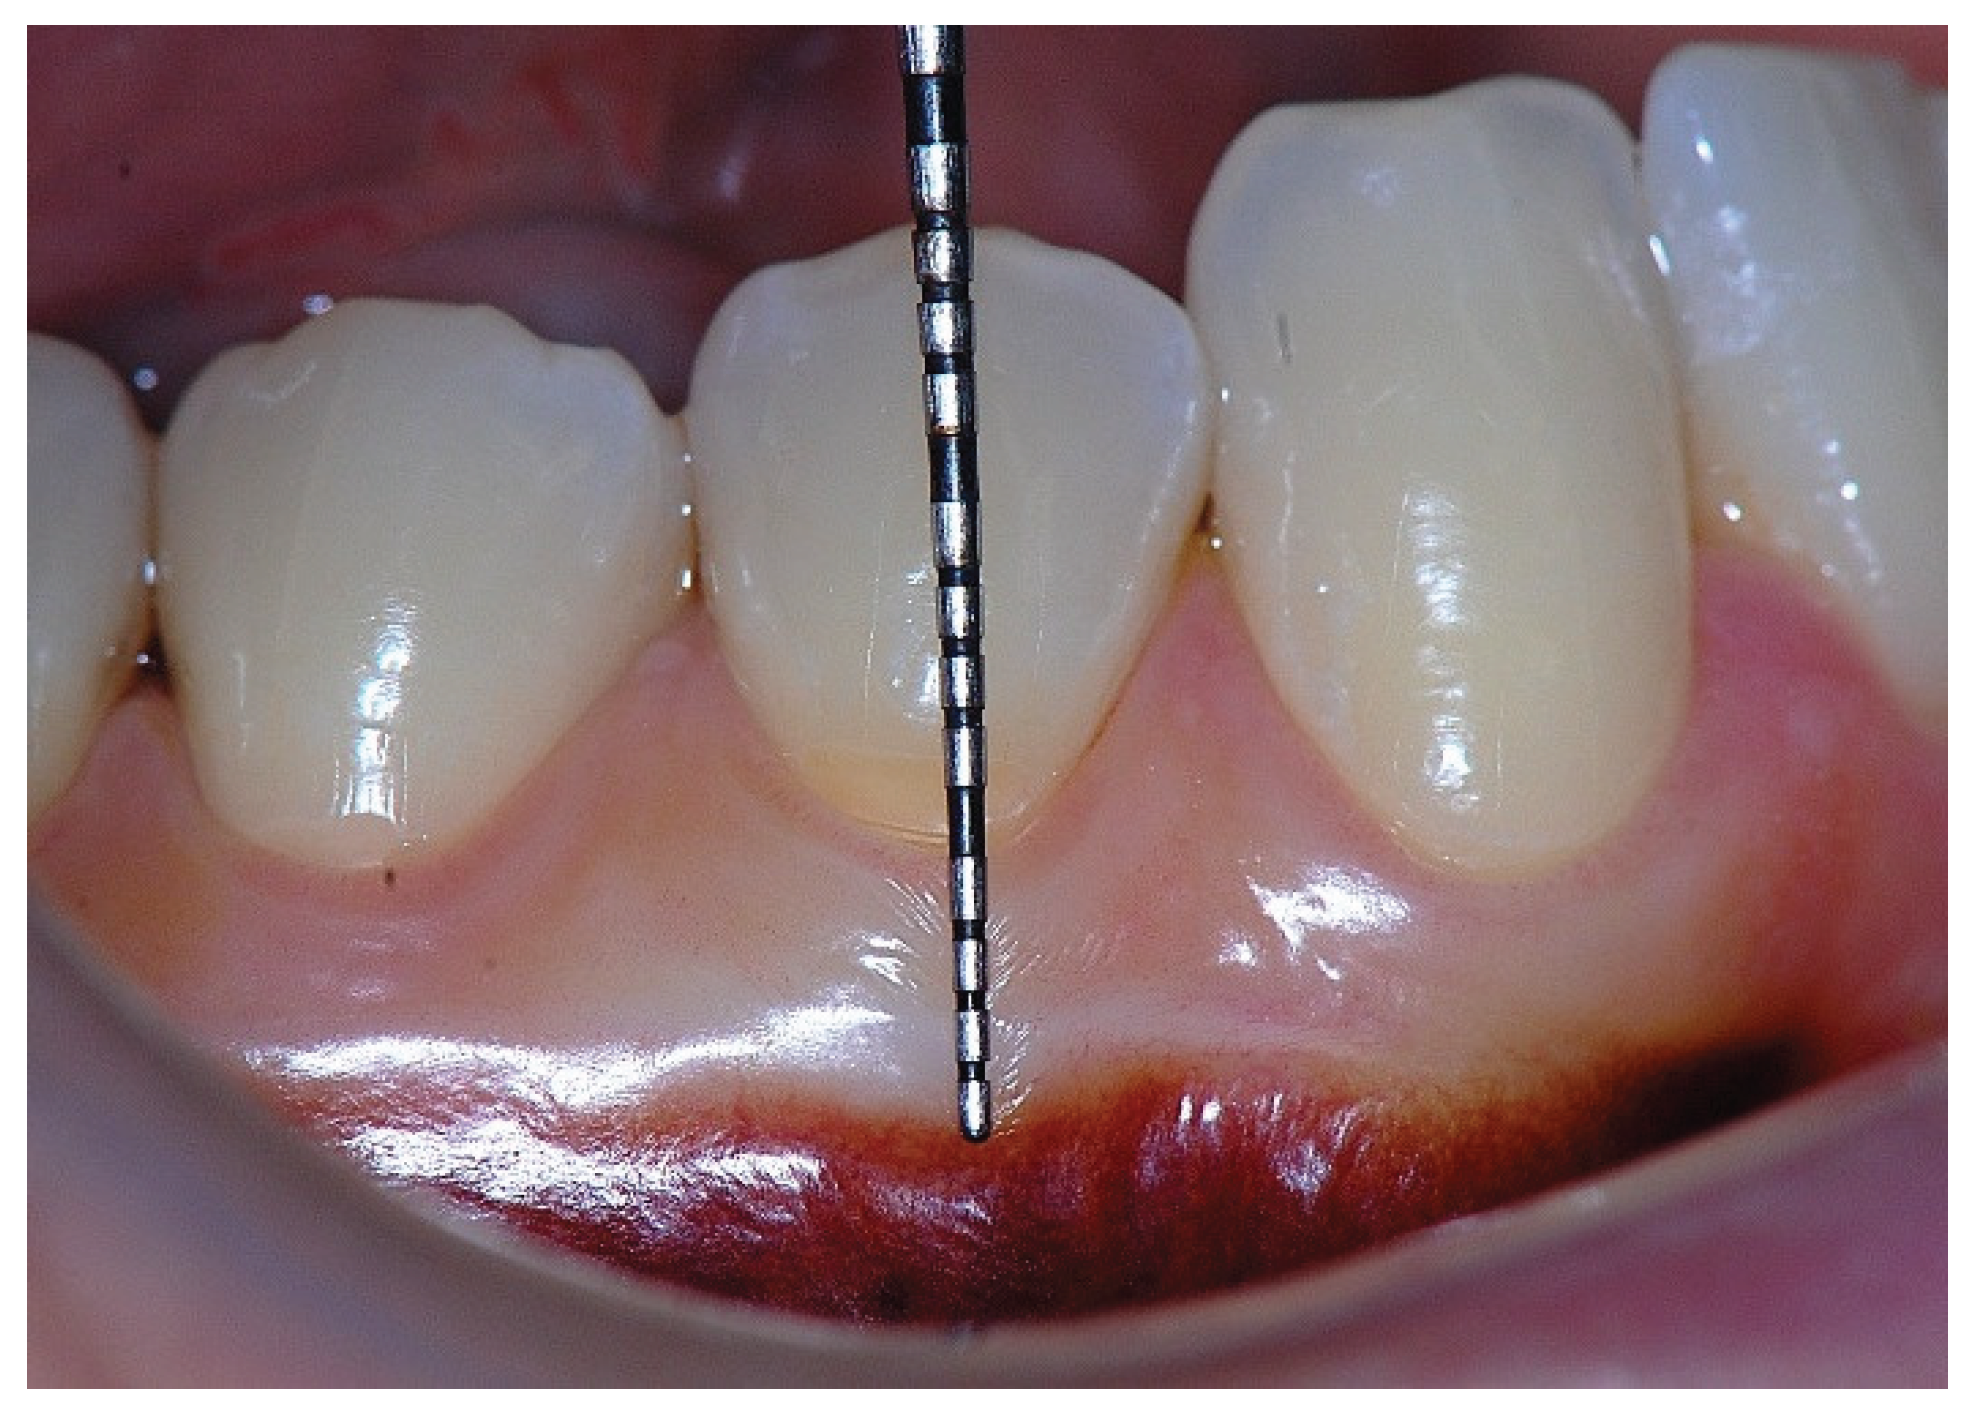

Figure 9. Probing depth of 1 mm demonstrating that the 1 mm band of attached gingiva corresponded primarily to epithelial attachment.

Figure 8. Clinical view showing a 2 mm band of keratinized tissue on the facial aspect.

Additionally, the direction and insertion pattern of the supracrestal connective tissue fibers relative to the keratinized tissue (KT) play a critical role in determining gingival margin stability, provided that the anatomical landmarks remain within normal limits (i.e., 1 mm of epithelial attachment and 1 mm of probing depth). (Figure 8, Figure 9, Figure 10, Figure 11 and Figure 12)

However, the ideal clinical scenario involves ≥3 mm of KT, as this supports connective tissue fiber insertion into both the root surface and the periosteum of the alveolar bone. (Figure 7, Figure 8, Figure 9, Figure 10 and Figure 11) Notably, a KT width ≥3 mm is the only condition that fully aligns with all descriptions of AG in the periodontal literature and with the AAP criteria, in which the AG must be firmly attached to the underlying alveolar bone and root cementum by dense connective tissue fibers [1,29,30,31]